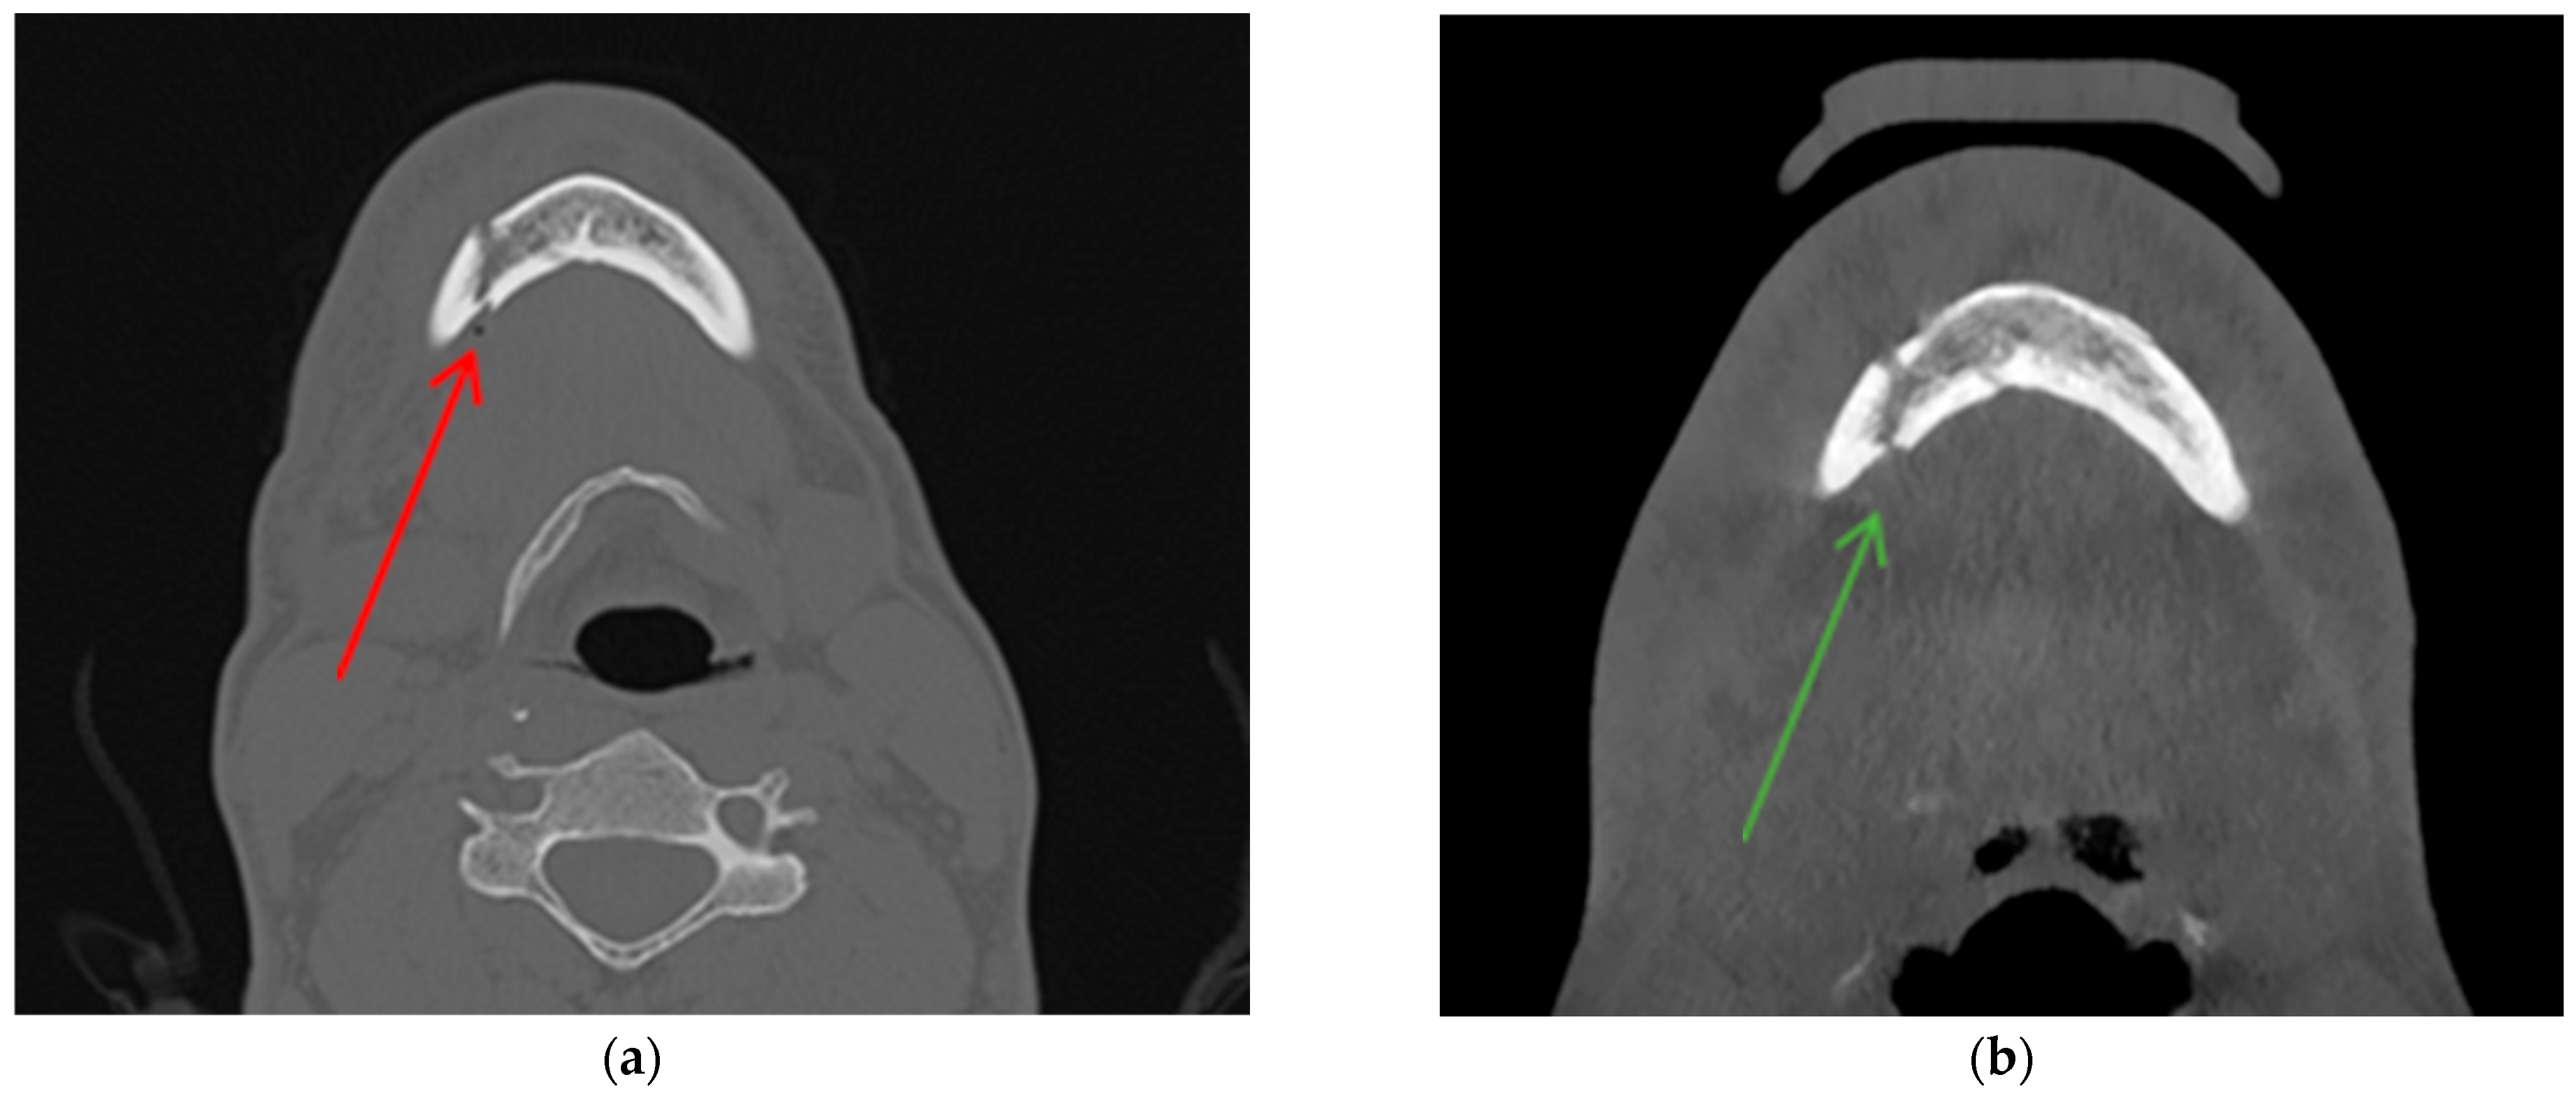

Diagnostic Utility of the “Air Sign” as a Radiological Indicator for Mandibular Body and Angle Fractures

- Gontarz, M.; Bargiel, J.; Gąsiorowski, K.; Marecik, T.; Szczurowski, P.; Zapała, J.; Wyszyńska-Pawelec, G. “Air Sign” in Misdiagnosed Mandibular Fractures Based on CT and CBCT Evaluation. Diagnostics 2024, 14, 362. [Google Scholar] [CrossRef]